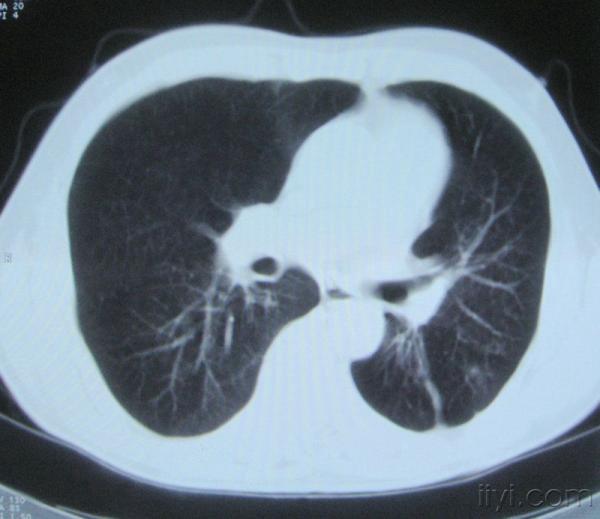

男。60岁,胸片示支气管炎治疗后复查CT。

你指那个肯定是淋巴结,中央系坏死,这很常见,特别在双侧腹股沟会经常看到。这个双侧腋窝及纵隔见多发小淋巴结征。

根据位置考虑应该是淋巴结,密度不均,是因为肿大的淋巴结中心液化坏死